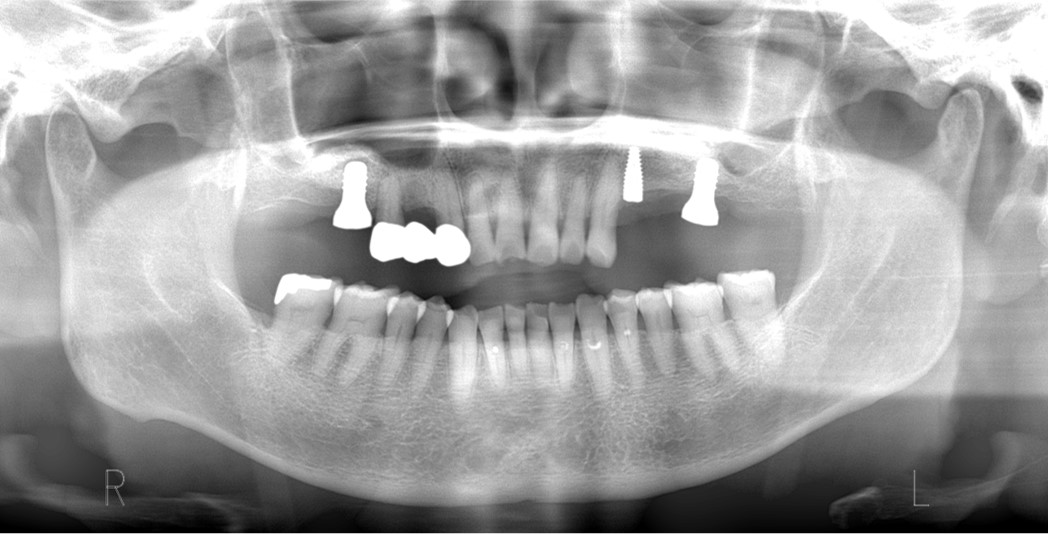

インプラント埋入のために、上顎の奥歯の骨の厚みが足りない場合に骨を作る処置です。もともとの骨の厚みにより、ソケットリフトもしくはサイナスリフトを選択します。骨を作る程度により治療内容や期間はさまざまです。

上顎の骨を持ち上げて同時にインプラントを埋入しました。